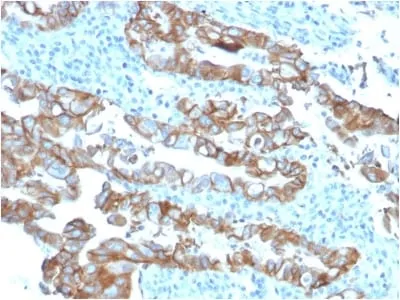

Anti-TACSTD2 / TROP2 (Epithelial Marker) (TACSTD2/2153), Biotin conjugate